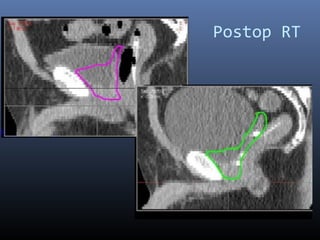

Postop RT